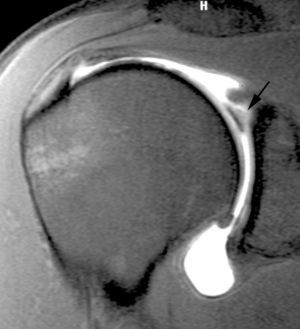

ALPSA (anterior labroliamentous periosteal avulsion)

Al igual que en el apartado anterior, existe también una separación de LG junto con la cápsula y el periostio, pero a diferencia de las lesiones de Bankart o Perthes, el LG se desplaza hacia dentro, por detrás del borde de la glenoides18 (fig. 12). La lesión de ALPSA puede cicatrizar por sinovialización (fig. 12), pero continúa siendo de carácter inestable.

Fig. 12.--ALPSA (anterior labroliamentous periosteal avulsion) agudo (A) y crónico (B). Nótese la separación del labio glenoideo y su desplazamiento posterior y medial por detrás del reborde glenoideo (flecha en A). En una fase crónica el labio glenoideo no se distingue como una estructura separada, sino como un engrosamiento de la unión entre el labio, la cápsula y el periostio (flecha en B).